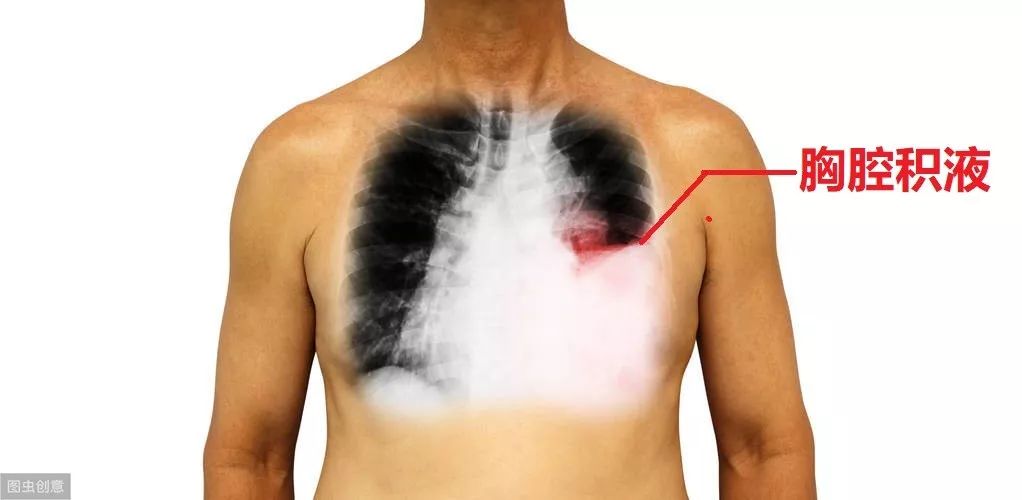

九、胸腔穿刺术

如果患者有肺炎、肺癌、肺结核,或者心力衰竭等,可能导致胸腔积液。所谓的胸腔积液,就是在胸腔里面积聚了液体。正常情况下,胸腔不应该有很多液体的,仅有一点点液体而已。但疾病状态下,比如肺癌,渗出液体会很多,这些液体就会落入胸腔,导致胸腔积液,或者积血。

胸腔积液的存在,会影响肺膨胀,影响通气,患者会觉得缺氧、气不够。为了解决这问题,我们需要进行胸腔穿刺术,把里面的液体抽出来。同时,可以把液体拿去化验,了解液体的性质,从而推测产生胸腔积液的病因。再针对病因治疗。

胸腔穿刺的过程比较简单,就是在两根肋骨之间进针,直接怼入胸腔里面,如果有液体出来,那就说名穿对地方了。很少情况下,可能会穿到血管,造成大出血。也可能穿到肺,把肺给捅破了,导致气胸。为了预防这些并发症,医生需要打起12分精神,严格按照操作规程。